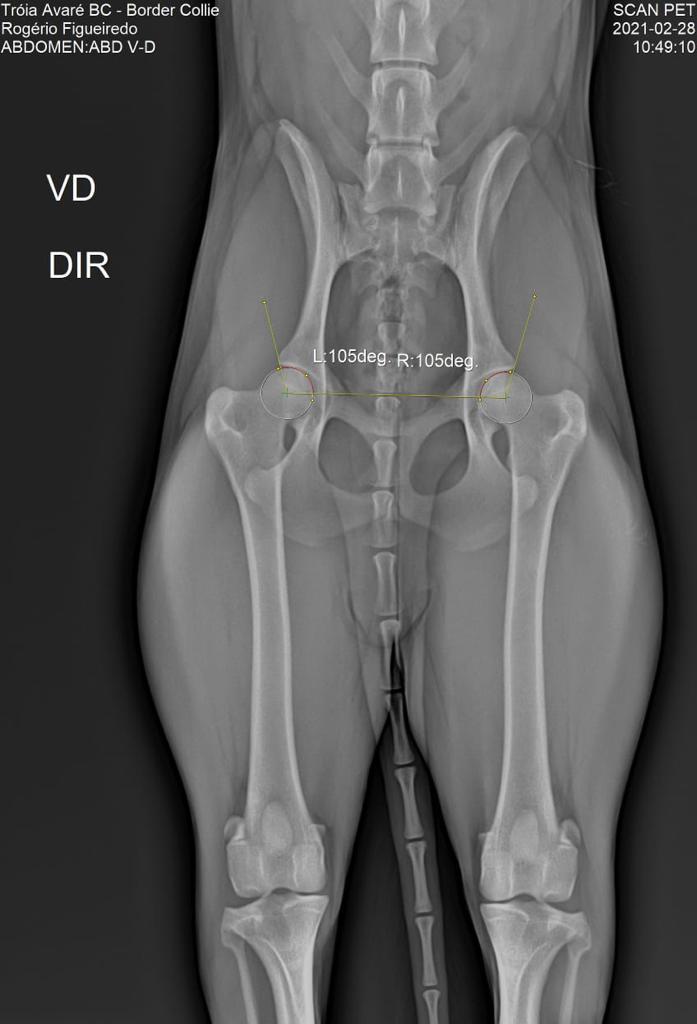

DISPLASIA

28/02/2021

ADEQUADO GRAU A

SCANPET

LAUDO

CHAPA